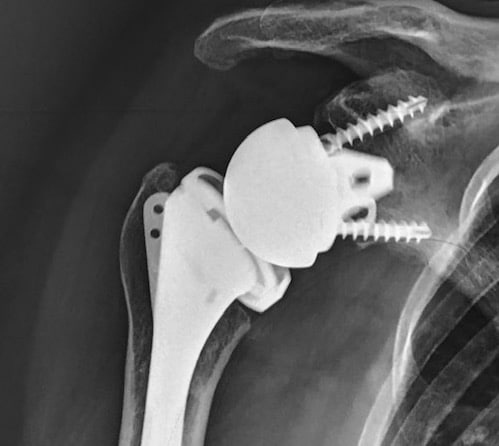

Prothèse anatomique

Prothèse totale inversée

Quelle prothèse d’épaule, dans quel cas ?

Cette intervention nécessite une courte hospitalisation mais peut, dans certains cas, être réalisée en ambulatoire. Elle permet une indolence et un gain des amplitudes articulaires dans la majeure partie des cas. Aujourd’hui, la longévité d’une prothèse est de 10 à 15 ans, 20 ans pour certains patients.